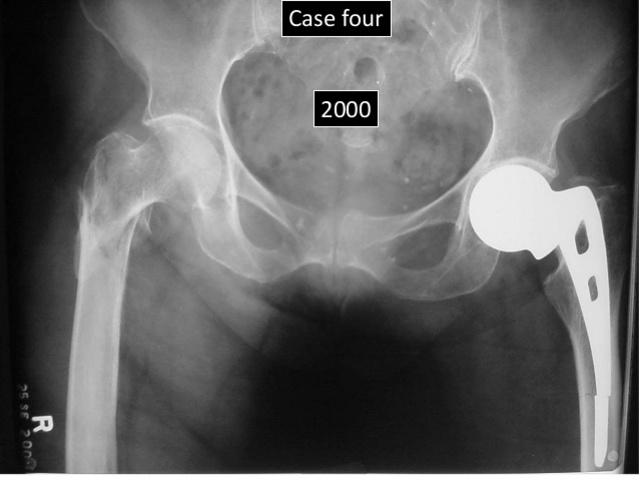

• AUSTIN T. MOORE (1899-1963)

AUSTIN T. MOORE (1899-1963)

publicó y realizó la primera sustitución metálica de la cadera, Había remplazado, por primera vez, toda la porción superior del fémur con una prótesis de vitalio de un pie de longitud. Tenía una cabeza esférica, ojales para la reinserción muscular, y un extremo distal que se deslizaba en la diáfisis rimada donde se fijaba con pernos. Con el transcurso de los años mejoró el diseño de la prótesis y el procedimiento. Existe un tipo de prótesis, la de Austin-Moore, que se utiliza aún hoy en día.

• EUSEBIO CADENA

realiza el primer remplazo de cadera en Colombia en el hospital san ignacio